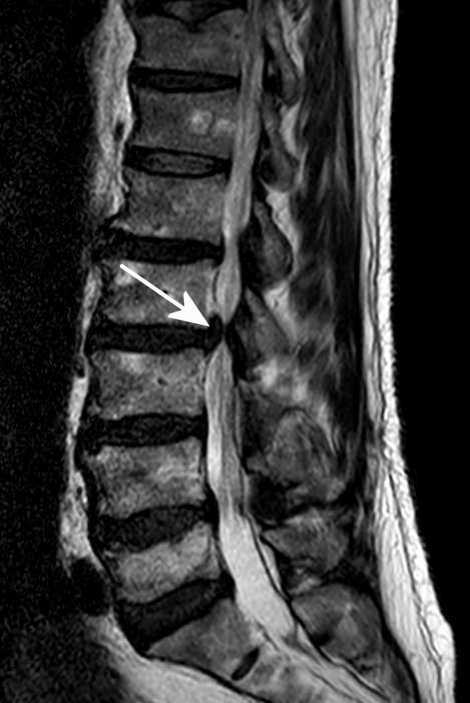

Abb.3: Durch Fehlhaltung und das nach vorn gekippte Becken verrutschte der unterste Wirbel in Richtung Bauchraum. Von der Bandscheibe darunter blieb nicht viel übrig.

Abb.4: Durch die stärkere Krümmung der Wirbelsäule werden Bandscheiben oder Wirbel keilförmig in Richtung Bauchraum gedrückt.